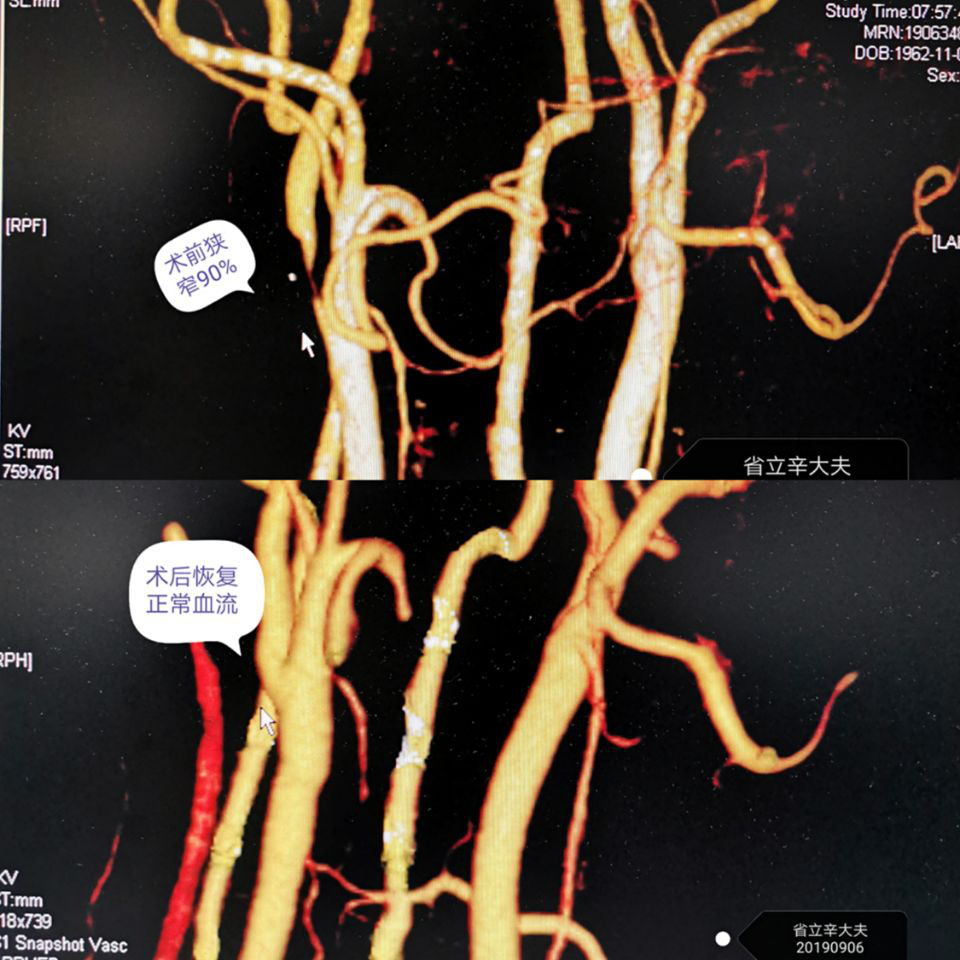

泉港患者柯先生因长期头晕乏力,脑血管供血不足,先后就诊多家医院,被明确诊断为右侧颈动脉重度狭窄,狭窄高达90%。当地医院建议其行颈动脉支架植入术(CAS),考虑到支架的高昂费用及需要后续的终生服药,柯先生始终犹豫不决。家属后来经多方打听,慕名至我院神经外科辛惠宁副主任医师处就诊。

经过充分的术前评估,在科室主任黄绳跃主任医师的支持下,辛惠宁副主任医师联合麻醉科、心血管外科、TCD、介入科等多学科团队,为患者成功剜除患者颈动脉增厚钙化的内膜组织,并在显微镜下缝合了血管。次日复查,柯先生颈动脉狭窄症状解除,脑缺血表现完全消失。出院时,家属激动地表示,“手术效果我们非常满意,不仅费用更低,而且不用终生服药,太好了!”